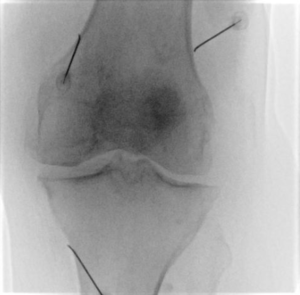

3. Les aiguilles de radiofréquences sont mises en place sous guidage, le nombre d'aiguille varie en fonction des procédures et des cas de figures.

4. Une fois en place, nous réalisons un test moteur et sensitif préalable pour s'assurer que les aiguilles soient correctement positionnées, notamment à distance des principaux nerfs moteurs.

5. Le chauffage au travers des aiguilles peut alors débuter et dure généralement 60 secondes par aiguilles.

Douleur de genou Scopie genou